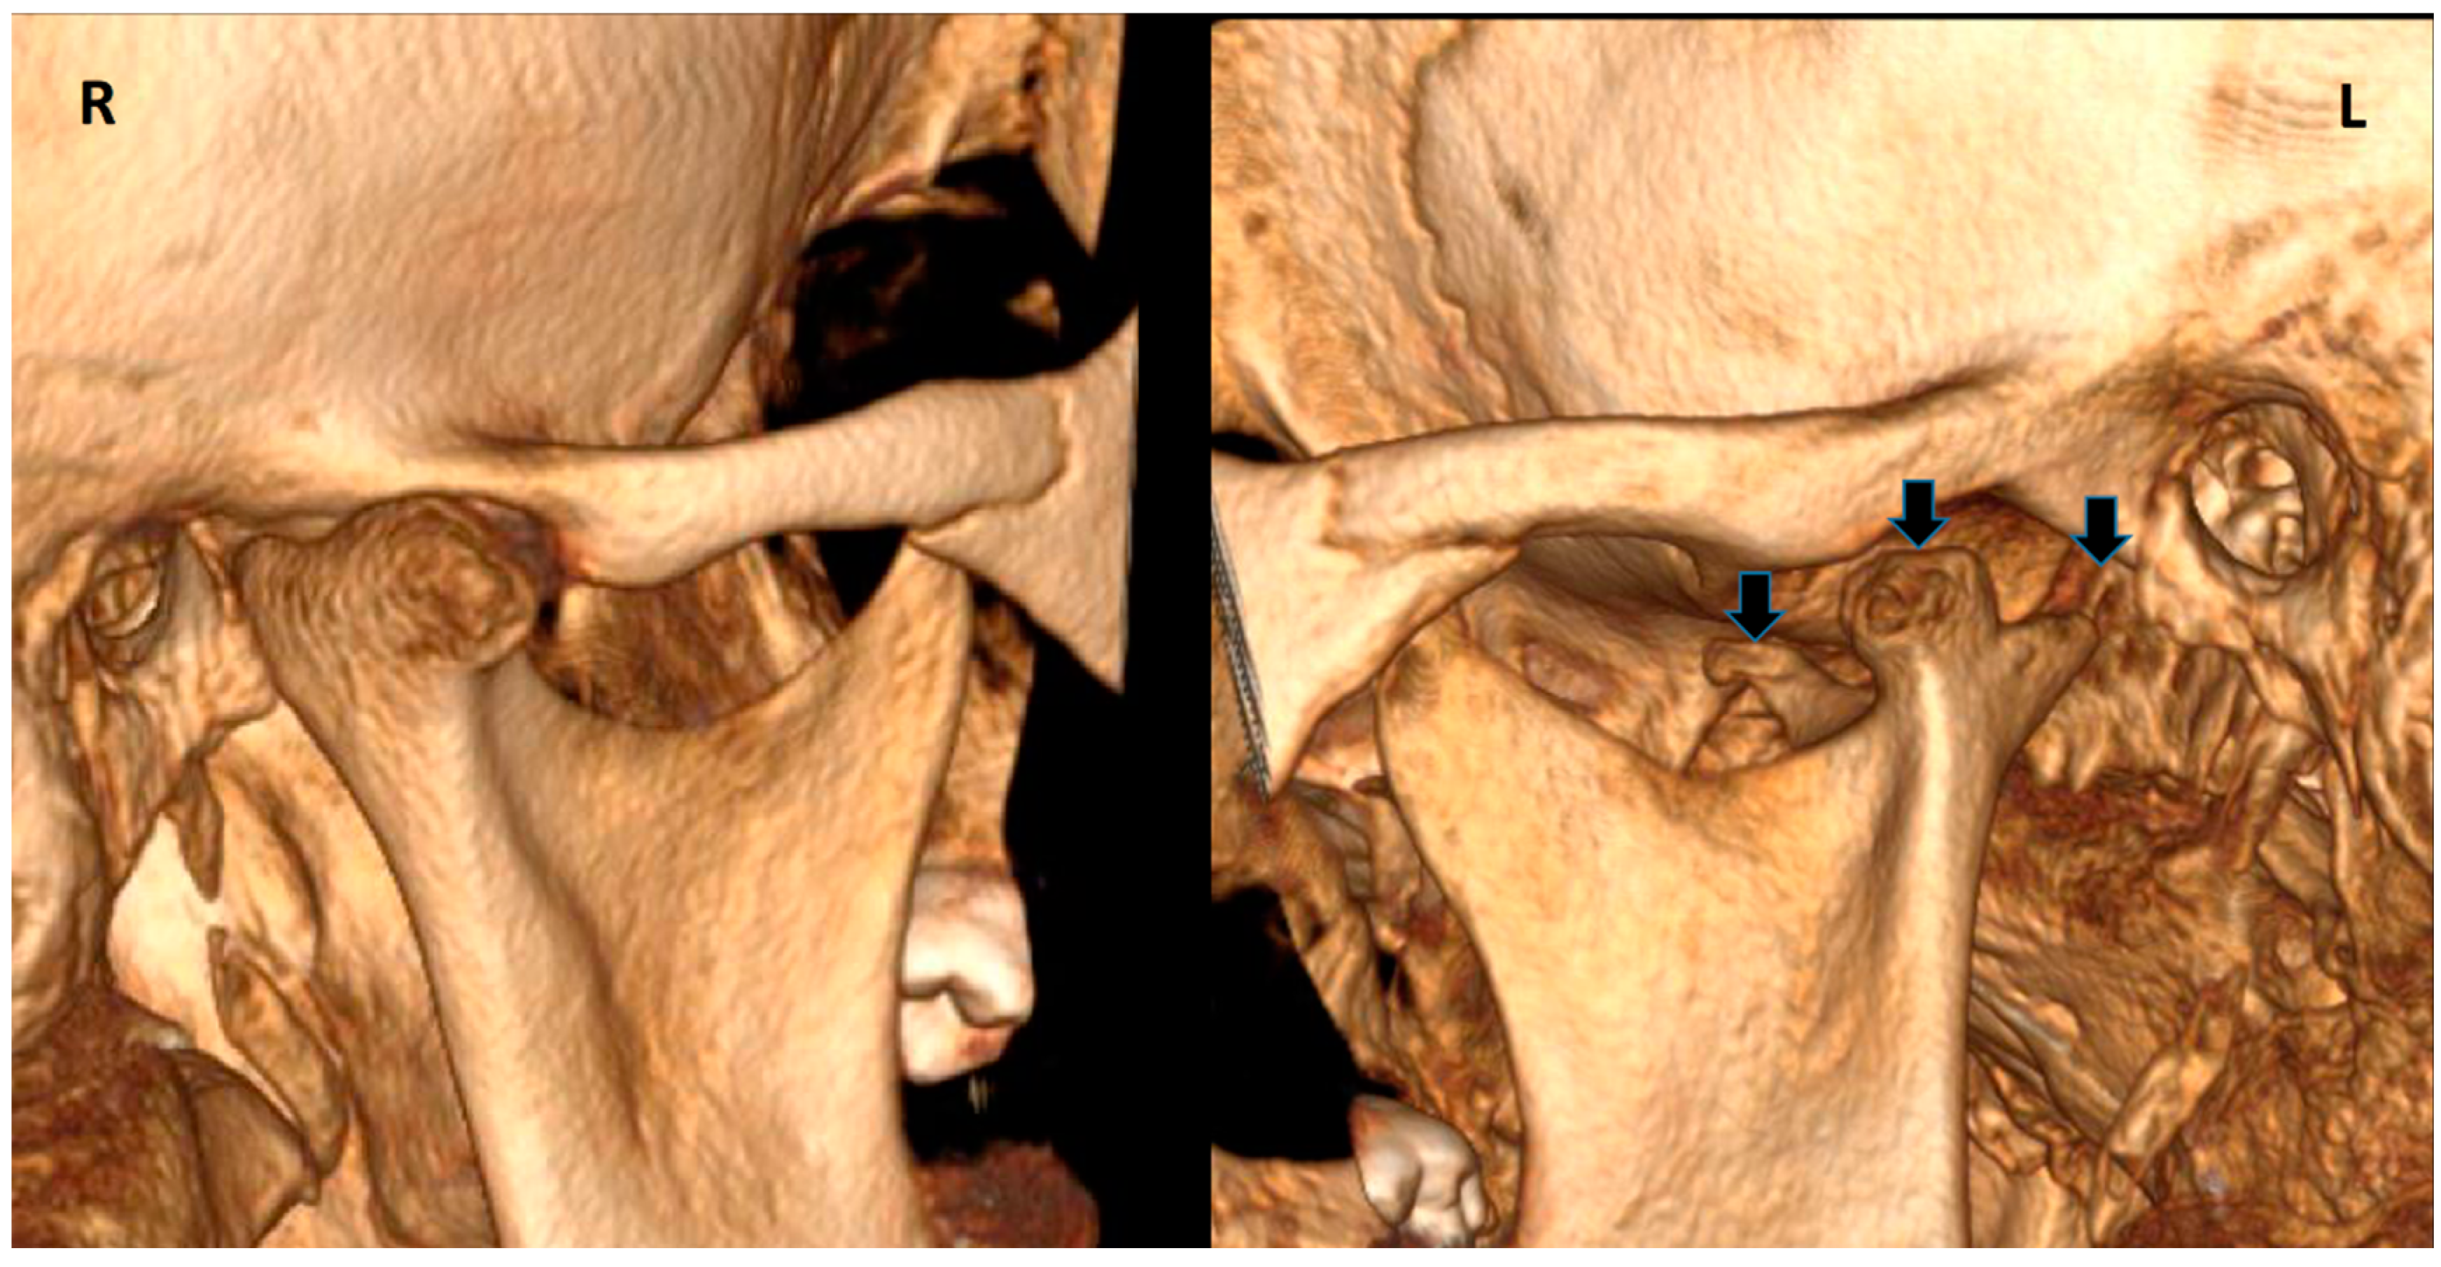

| Sezgin & Katipman 2009 [3] | M, 31 | Mandible deviated to the right | Trauma | FU | - |

| Prasanna T. et al., 2015 [1] | F, 26 | Mild facial asymmetry, micrognathia & deviation of the mandible to left | - | None | - |

| Hernández-Andara A. et al., 2017 [8] | M, 12 | Facial asymmetry & a clicking noise in the left TMJ | Trauma | FU | - |